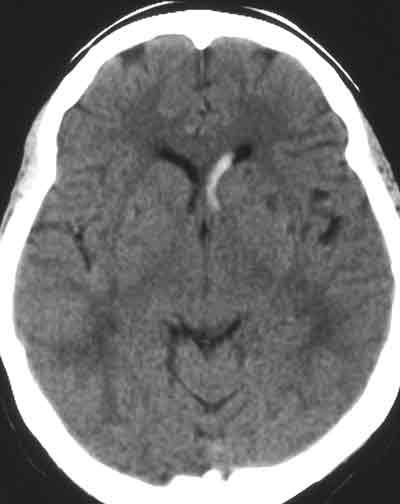

A 37-year-old woman who had hypertension presented with a diffuse, sharp, pounding headache. A noncontrast head CT scan showed a hemorrhage in the frontal horn of the lateral ventricle. This second slice showed a left intracranial cerebral hemorrhage in the basal ganglia region that extends into the lateral ventricle. Sudden onset of headache suggests intracranial or subarachnoid hemorrhage. Intracranial hemorrhage often is associated with a profound reactive rise in blood pressure.

Image courtesy of Gary Quick, MD and Maggie Law, MD.